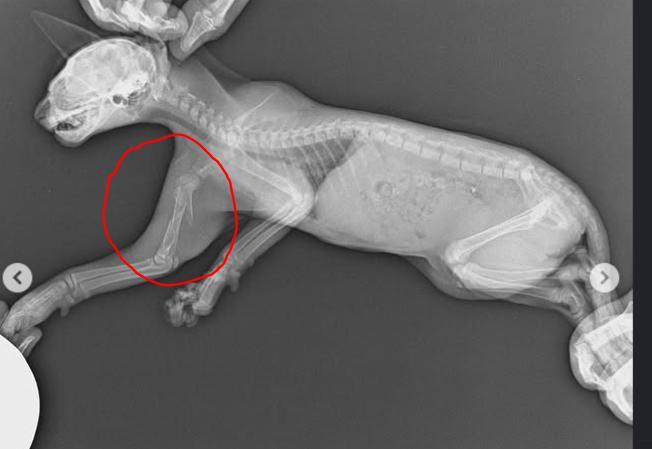

Urgente: Ayuda gatete atropellado

Ayer recibimos un aviso de un gatete que había sido atropellado en la calle Delicias (Madrid). Estaba solito, en medio de los coches… Lo rescatamos de inmediato y lo llevamos al veterinario de Mascoteros en Rivas Vaciamadrid, donde confirmaron que tiene roto el húmero.

Ahora se encuentra en nuestro refugio, tomando antiinflamatorios y con todos nuestros cuidados ❤️. Mañana volverá al veterinario para que el traumatólogo valore si puede ser operado.

Necesitamos de vuestra ayuda para que este pequeñín tenga la oportunidad de ser operado y disfrutar de un hogar feliz ✨.

Nuestra pequeñita ayer pasó por una operación de húmero. Ahora está adolorida, pero con muchísima fuerza y valentía ✨. Confiamos en que pronto se recupere y pueda comenzar una nueva vida, llena de amor y cariño en el calor de un hogar .